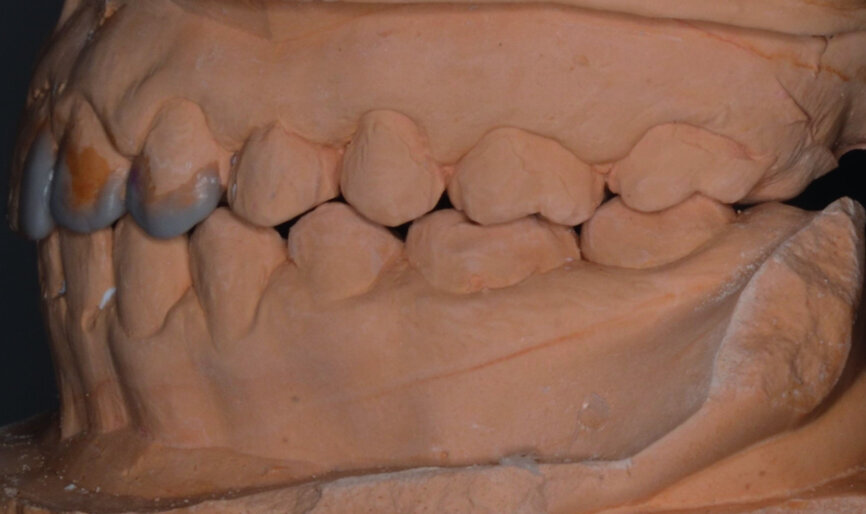

- Initial CR mounting (Figs. 19–21).

Finally space analysis was carried out (Tables 1a & b).

At the end of orthodontic treatment, gingival margins were well aligned, midlines were centred and canines and first premolars were positioned to facilitate the restorative phase of treatment (Figs. 34–36). At this phase, a final CR mounting and wax-up was performed (Figs. 37–39), as well as the anterior teeth restorations (Fig. 40).